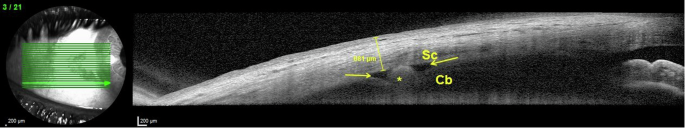

Spectral-domain OCT scans of the retina and supraciliary space were performed using the Spectralis OCT (Heidelberg Engineering GmbH; Heidelberg, Germany). To verify the correct placement of the DEX implant within the supraciliary space, OCT images of the anterior sclera, encompassing the implantation site, were acquired using enhanced depth imaging mode. Reference points were used at baseline and follow-up retinal OCT acquisitions. Spectralis OCT was configured to perform volume scans with dimensions of 30° × 25°, consisting of 32 lines with 512 A-scans per line for macular cube measurements. ETDRS subfield measurements were obtained using the already built-in Spectralis software. The algorithm utilised the average macular thickness measurements from 4 macular quadrants and 3 concentric circles with diameters of 1 mm, 3 mm, and 6 mm [13]. The maximum retinal thickness (MRT) was defined as the highest value among these quadrants. Central retinal thickness changes (ΔCRT) were assessed within the central fovea subfield of the 1-mm diameter circle. ΔCRT was calculated by subtracting the postoperative central retinal thickness from the preoperative central retinal thickness [ΔCRT = (preoperative CRT) − (postoperative CRT)].

SC-DEX implants were visualised in all eyes after SC injections using anterior segment OCT (Fig. 3). Fortunately, no cases of suprachoroidal haemorrhage, choroidal detachment, ciliary body detachment, or endophthalmitis were observed in either group. Nine patients (47.3%) in the SC-DEX group reported pain during injections, and all eyes in this group developed subconjunctival haemorrhage. Among these eyes, 4 (21%) had haemorrhage in 1 quadrant, 13 (68.4%) had haemorrhage in 2 quadrants, and 2 (10.5%) had haemorrhage in 3 quadrants. The progression of cataract could not be assessed in either group due to the short follow-up of the study.

The results in our study showed that anterior segment OCT can be used as a tool to monitor the placement of the SC implant. Here in our cases, SC-DEX treatment was well tolerated and anatomical and visual efficacy and safety parameters were comparable to that of IV-DEX treatment. BCVA levels were significantly better in the SC-DEX group compared to the IV-DEX group during the first week of injections (p = 0.014). When considering both groups, although baseline BCVA was not statistically significant, the lower BCVA in the IV-DEX group may have contributed to the limited improvement after the IV-DEX injection, which differed from the literature [24]. No differences were observed between the two groups at any visit in terms of IOP fluctuations. However, due to the short follow-up period of the study, cataract progression could not be assessed in either group.